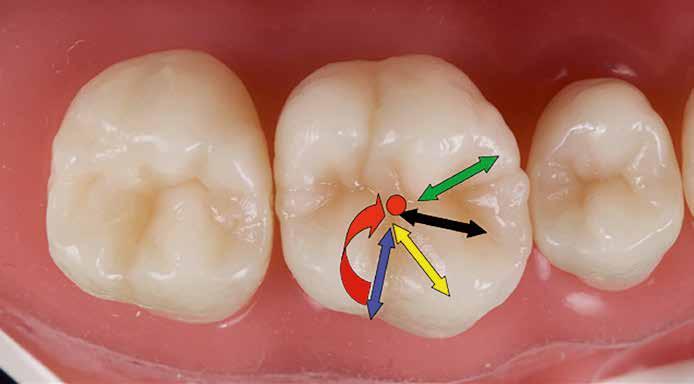

Posselt az állkapocs funkcionális mozgásait a mandibula határmozgásainak görbéjével (Posselt-féle diagram) írta le, amely három térbeli síkra bontható (1. ábra): sagittális, frontális és horizontális. Ebből következik, hogy a fogak dinamikus kölcsönhatása is három dimenzióban értelmezhető [7].

Az egyes csücskök háromdimenzóban végzett, funkcionális mozgáspályáinak összességét nevezzük okkluzális iránytűnek (2. ábra). Az okkluzális iránytű minden csücsök esetében egyedi (a rajta lévő bemélyedések és kiemelkedések szempontjából), és azt a csücsöknek a mandibula condylusának forgásközéppontjához viszonyított helyzete határozza meg.

Az okkluzális iránytű leírásához használt terminológia a The Glossary of Occlusal Terms-ből származik, amelyet a The Glossary Committee of The International Academy of Gnathology állított össze [8]. Fontos megjegyezni, hogy a mandibula mozgásai rágás és nyelés során mindig a maximális interkuszpidációs helyzetből indulnak ki, és oda is térnek vissza.

Ezek a mozgások a következők:

• PROTRUSIO (fekete) – az állkapocs előrefelé irányuló mozgása;

• LATEROTRUSIO (kék) – oldalirányú vagy kifelé történő mozgás;

• LATEROPROTRUSIO (sárga) – kifelé és előre irányuló mozgás kombinációja;

• LATERORESURTRUSIO (piros) – kifelé, hátrafelé és felfelé irányuló mozgás. Ez a mozgás Bennett-mozgásként ismert, Norman G. Bennett (1870–1947) után elnevezve;

• MEDIOTRUSIO (zöld) – mesiális oldalirányú, befelé történő mozgás, amely lehetővé teszi az ellenkező oldali condylus lefelé/előre irányuló mozgását [9].

Az iránytű középpontja (az IKP-ben létrejövő érintkezés) körül található egy kisebb szabad zóna, amely lehetővé teszi az antagonista csücsök mozgását a „hosszú centrikus” (Long Centric vagy Freedom in Centric) tartományban [10]. Ez képezi a Polz-féle biomechanikai wax-up [11] alapját, amelyre a DeVreugd-féle okkluzális iránytű is épül. Jelen publikáció célja egy dinamikus alapú, ésszerű megközelítés bemutatása a hátsó fogak direkt kompozittal történő restaurálásához, amelynek eredményeként a rétegezést követően csupán minimális utólagos korrekcióra van szükség. A szerző a rövidebb, lényegre törő bemutatás kedvéért a felső első molárisra fókuszál. Ezt a fogat azért választotta, mert rágás közben ez viseli a legnagyobb erőbehatást, és ezen a fogon található a legtöbb okklúziós érintkezési pont [9].

DeVreugd-féle okkluzális iránytű.

1. ábra: Posselt-féle állkapocsmozgási görbe.

2. ábra: